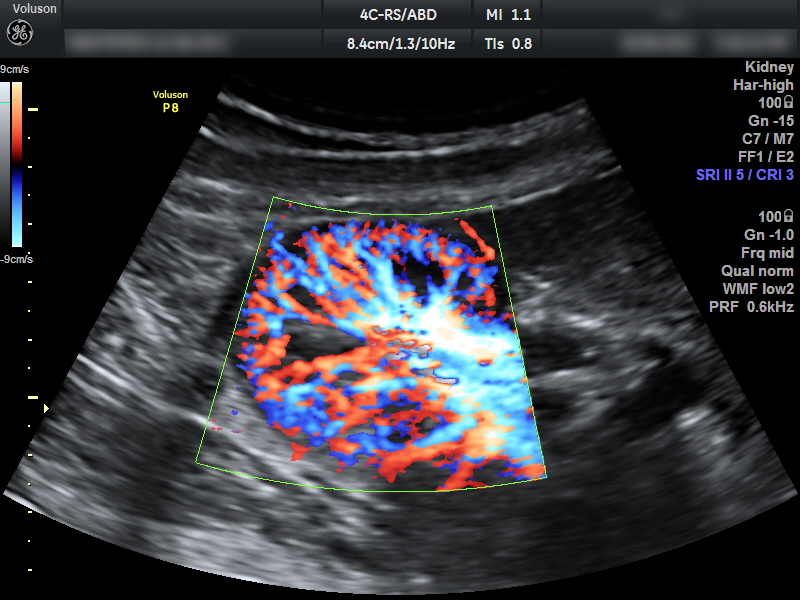

Ультразвуковая допплерография почечных артерий (УЗДГ) – метод обследования кровеносных сосудов и особенностей их функционирования: диаметра, строения, скорости кровотока. Изменение скорости или направления крови возможно из-за спазма сосуда, тромбоза, атеросклеротических бляшек, потери тонуса и эластичности стенки.

За сутки почки фильтруют 1700-2000 литров крови, поэтому важно своевременно выявлять сосудистые нарушения.